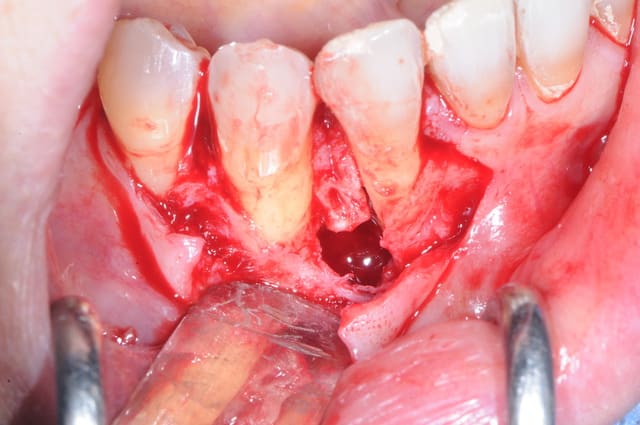

les photos de l'intervention...

photo 1-2-3 ouverture et extraction de 42 puis par la suite de 43 car l'étendu de l'infection était trop importante

09/07/2014 à 14h40

1: petit bout d'os entre l'incisive et la canine

2: le défaut osseux

3 début de la dissection du nerf

4 je remonte du trou mentonier en direction de l'origine du kyste

5-8 une partie du kyste se trouvait inta osseux et extra osseux sur la table externe mandibulaire

le plus dure c'est de faire la différence entre la membrane du kyste et le nerf lui même